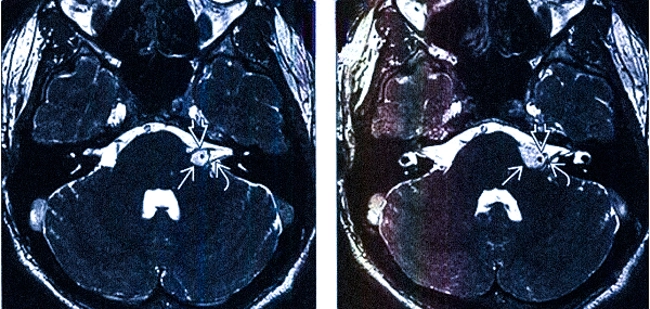

МРТ головного мозга. Т1-взвешенный аксиальный снимок (часть). Мосто-мозжечковые углы в норме. Цветовая коррекция изображения.